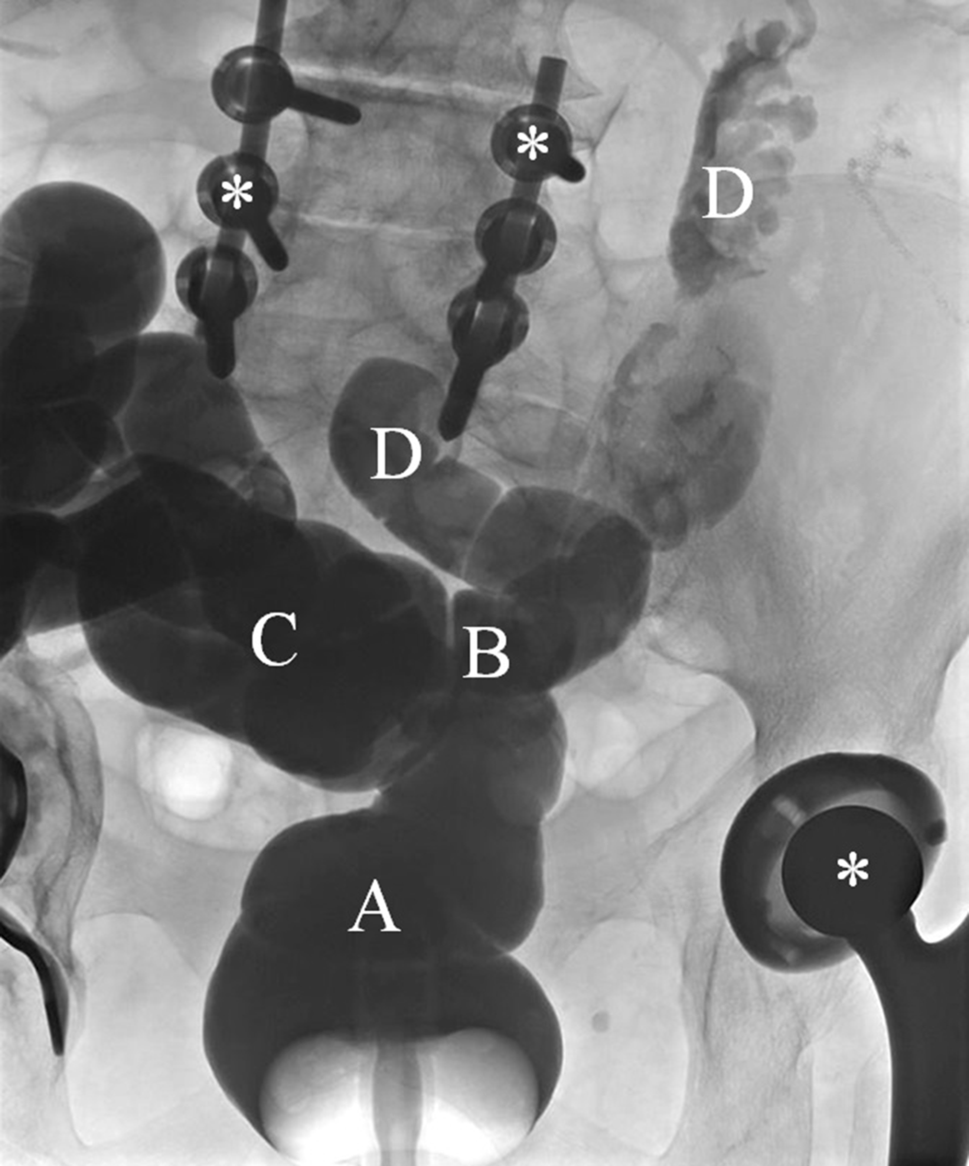

Dr. H. Wenzl: The remarkable discrepancy between the endoscopy report and the histologic findings prompted us to perform a barium enema in order to clarify the postoperative anatomy in our patient. The investigation revealed an enterocolonic fistula adjacent to the colorectal anastomosis (Fig. 1), which had apparently developed during the last 6 months due to ongoing inflammation after surgery for complicated diverticulitis 6 years earlier.

Fig. 1

Barium enema performed with special attention in search of an abnormal connection between the colon and small intestine: A rectum, B fistula connecting the proximal rectum and small bowel, C descending colon, D small bowel, asterisks: metal from hip replacement and lumbosacral stabilization which caused artifacts on CT scan